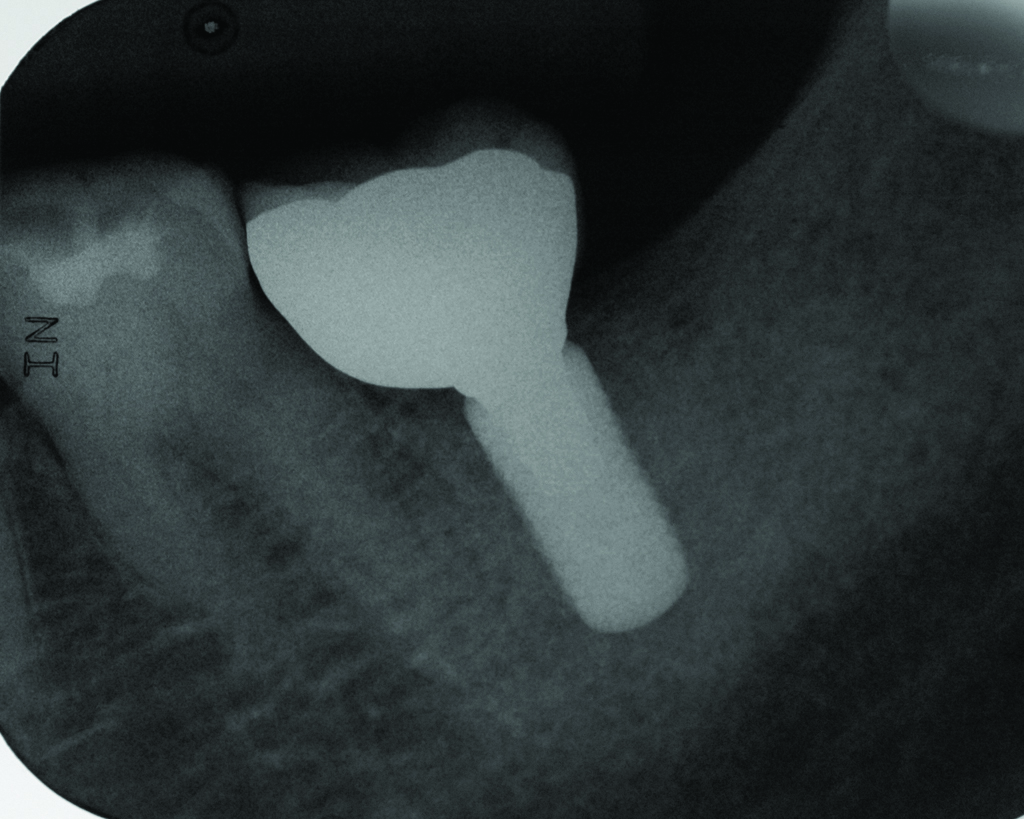

Figure 1

Radiograph of this same area. Note that there is no indication of bone loss and a long abutment collar. Hence, the diagnosis of peri-implant mucositis is given.